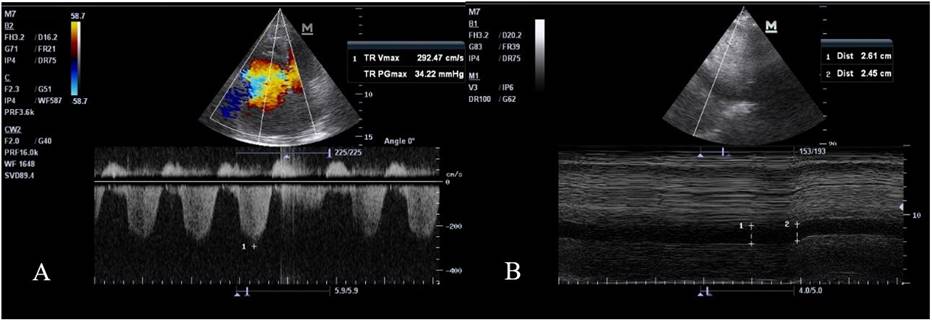

Se realiza electrocardiograma, donde se aprecia un ritmo sinusal y patrón S1Q3T3. Además, se practica un ecocardiograma al pie de cama (figura 1) donde se halla: vena cava inferior de 26 mmHg sin colapso inspiratorio (indicativo de presión en la aurícula derecha de 20 mmHg). Insuficiencia tricúspidea que permite estimar un gradiente de 34,9 mmHg. Que más la suma de la aurícula derecha, se estima una presión sistólica de la arteria pulmonar (PSAP) de 54 mmHg - presión media de la arteria pulmonar (PMAP) de 35,4 mmHg (hipertensión pulmonar severa utilizando la fórmula de Chemla). Se objetiva además signo de McConnell.

A. Gradiente de insuficiencia tricúspidea; B. Vena cava

Figura 1. Ecocardiograma y Ecofast

El ecocardiograma realizado demostró una presión sistólica de la arteria pulmonar (PSAP) de 54 mmHg. Las guías clínicas nos indican que ante una sospecha de HTP se puede utilizar una combinación de TRV (velocidad de regurgitación tricuspídea) y PASP, para orientar el diagnóstico. Un estudio demostró que su utilidad es moderada con respecto al cateterismo cardiaco derecho, pero se recomienda en ausencia del mismo.(5) La Sociedad Europea de Cardiología y la Sociedad Internacional de Trasplante de Corazón y Pulmón sugieren que la HTP es muy probable si la PASP es >50 mmHg.(6)

La HTP se clasifica en cinco grupos, según la etiología y el mecanismo. En nuestra paciente se sugiere un origen cardiaco, debido a una alteración – evidenciada en eco doppler - de la presión auricular derecha, acompañada de una insuficiencia tricuspídea. Por lo tanto, desde el punto de vista hemodinámico, más lo hallazgos encontrados, una presión arterial pulmonar media (PAPm; en decúbito supino y en reposo) de >20 mmHg se considera diagnóstica.(7)

El ecocardiograma en TEP nos podría ayudar a estratificar el riesgo y definir el pronóstico. Sobre todo, es muy sugestivo de TEP la disfunción del ventrículo derecho, que en el caso de la paciente se demostraba ante la prueba de imagen. Este estudio también nos ayuda a distinguir la sobrecarga aguda por TEP de una disfunción crónica por HTP.(11)